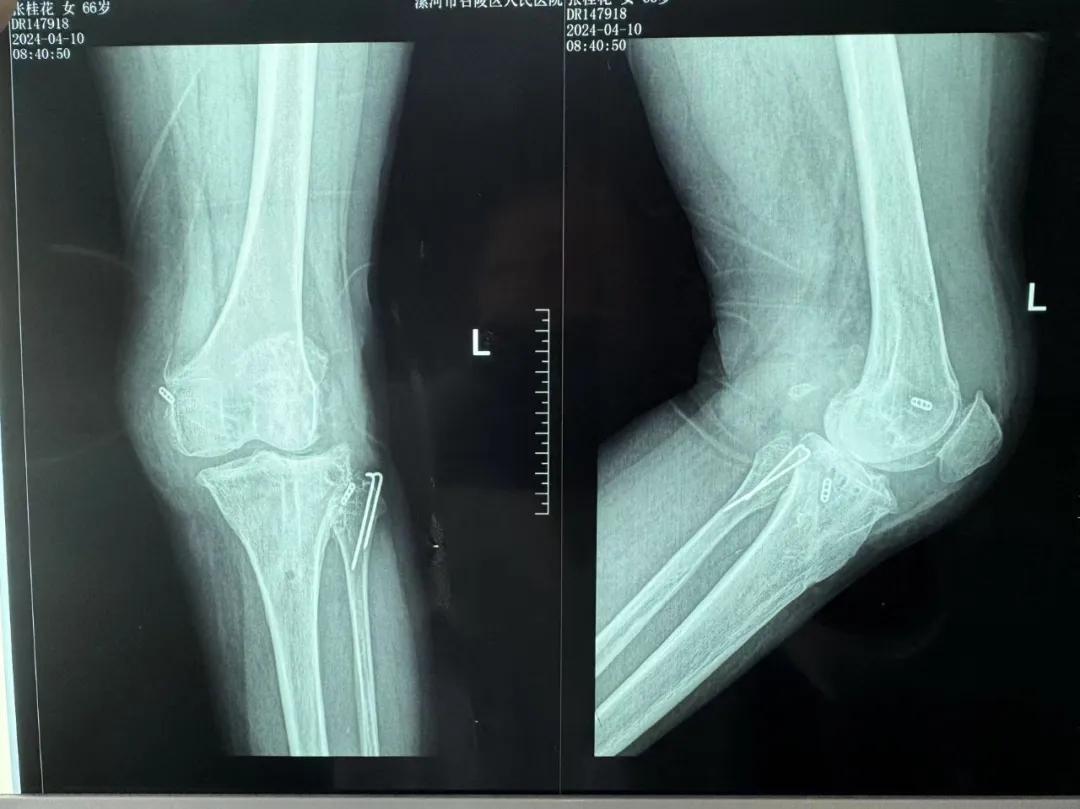

患者來院后,漯河市骨科醫(yī)院(漯河醫(yī)專二附院、漯河市立醫(yī)院)主治醫(yī)師康樂便成了她的管床醫(yī)生。在經(jīng)過詳細的術(shù)前診斷與檢查后,關(guān)節(jié)外科主任李付彬組織科室團隊針對患者的診斷情況進行術(shù)前討論——患者為重度膝關(guān)節(jié)骨關(guān)節(jié)炎,需進行人工關(guān)節(jié)置換。但術(shù)前的評估結(jié)果顯示:患者膝關(guān)節(jié)側(cè)方不穩(wěn)定,單純行初次表面膝關(guān)節(jié)置換,術(shù)后仍會存在側(cè)方不穩(wěn)的情況,會影響術(shù)后效果以及假體使用年限,不僅無法完全恢復膝關(guān)節(jié)功能,還會加重患者的經(jīng)濟負擔。

為了盡可能給患者帶來更好的治療效果,減輕其經(jīng)濟負擔,經(jīng)綜合評估后,李付彬主任帶領(lǐng)團隊制定了最終的手術(shù)方案——決定使用髁限制性膝關(guān)節(jié)假體(LCCK)置換膝關(guān)節(jié)。作為解決患者病痛的最優(yōu)方案,這項手術(shù)具體實施的難度并不小,需要在術(shù)中根據(jù)截骨情況進行多次評估和實時調(diào)整,這就要求主刀醫(yī)生不僅要具備過硬的專業(yè)技術(shù)與能力,還要能夠結(jié)合自身的經(jīng)驗準確判斷、精準操作。

手術(shù)過程中,關(guān)節(jié)外科團隊為患者進行了標準截骨,經(jīng)過評估,患者膝關(guān)節(jié)仍存在膝關(guān)節(jié)側(cè)方不穩(wěn)定,便按照原定手術(shù)計劃使用LCCK假體進行了膝關(guān)節(jié)置換。經(jīng)過再次評估,患者膝關(guān)節(jié)穩(wěn)定性恢復,下肢力線正常,這臺高難度的LCCK膝關(guān)節(jié)置換手術(shù)在一小時內(nèi)便順利完成!術(shù)后第二天,患者就能夠自主下床負重活動,功能恢復良好。